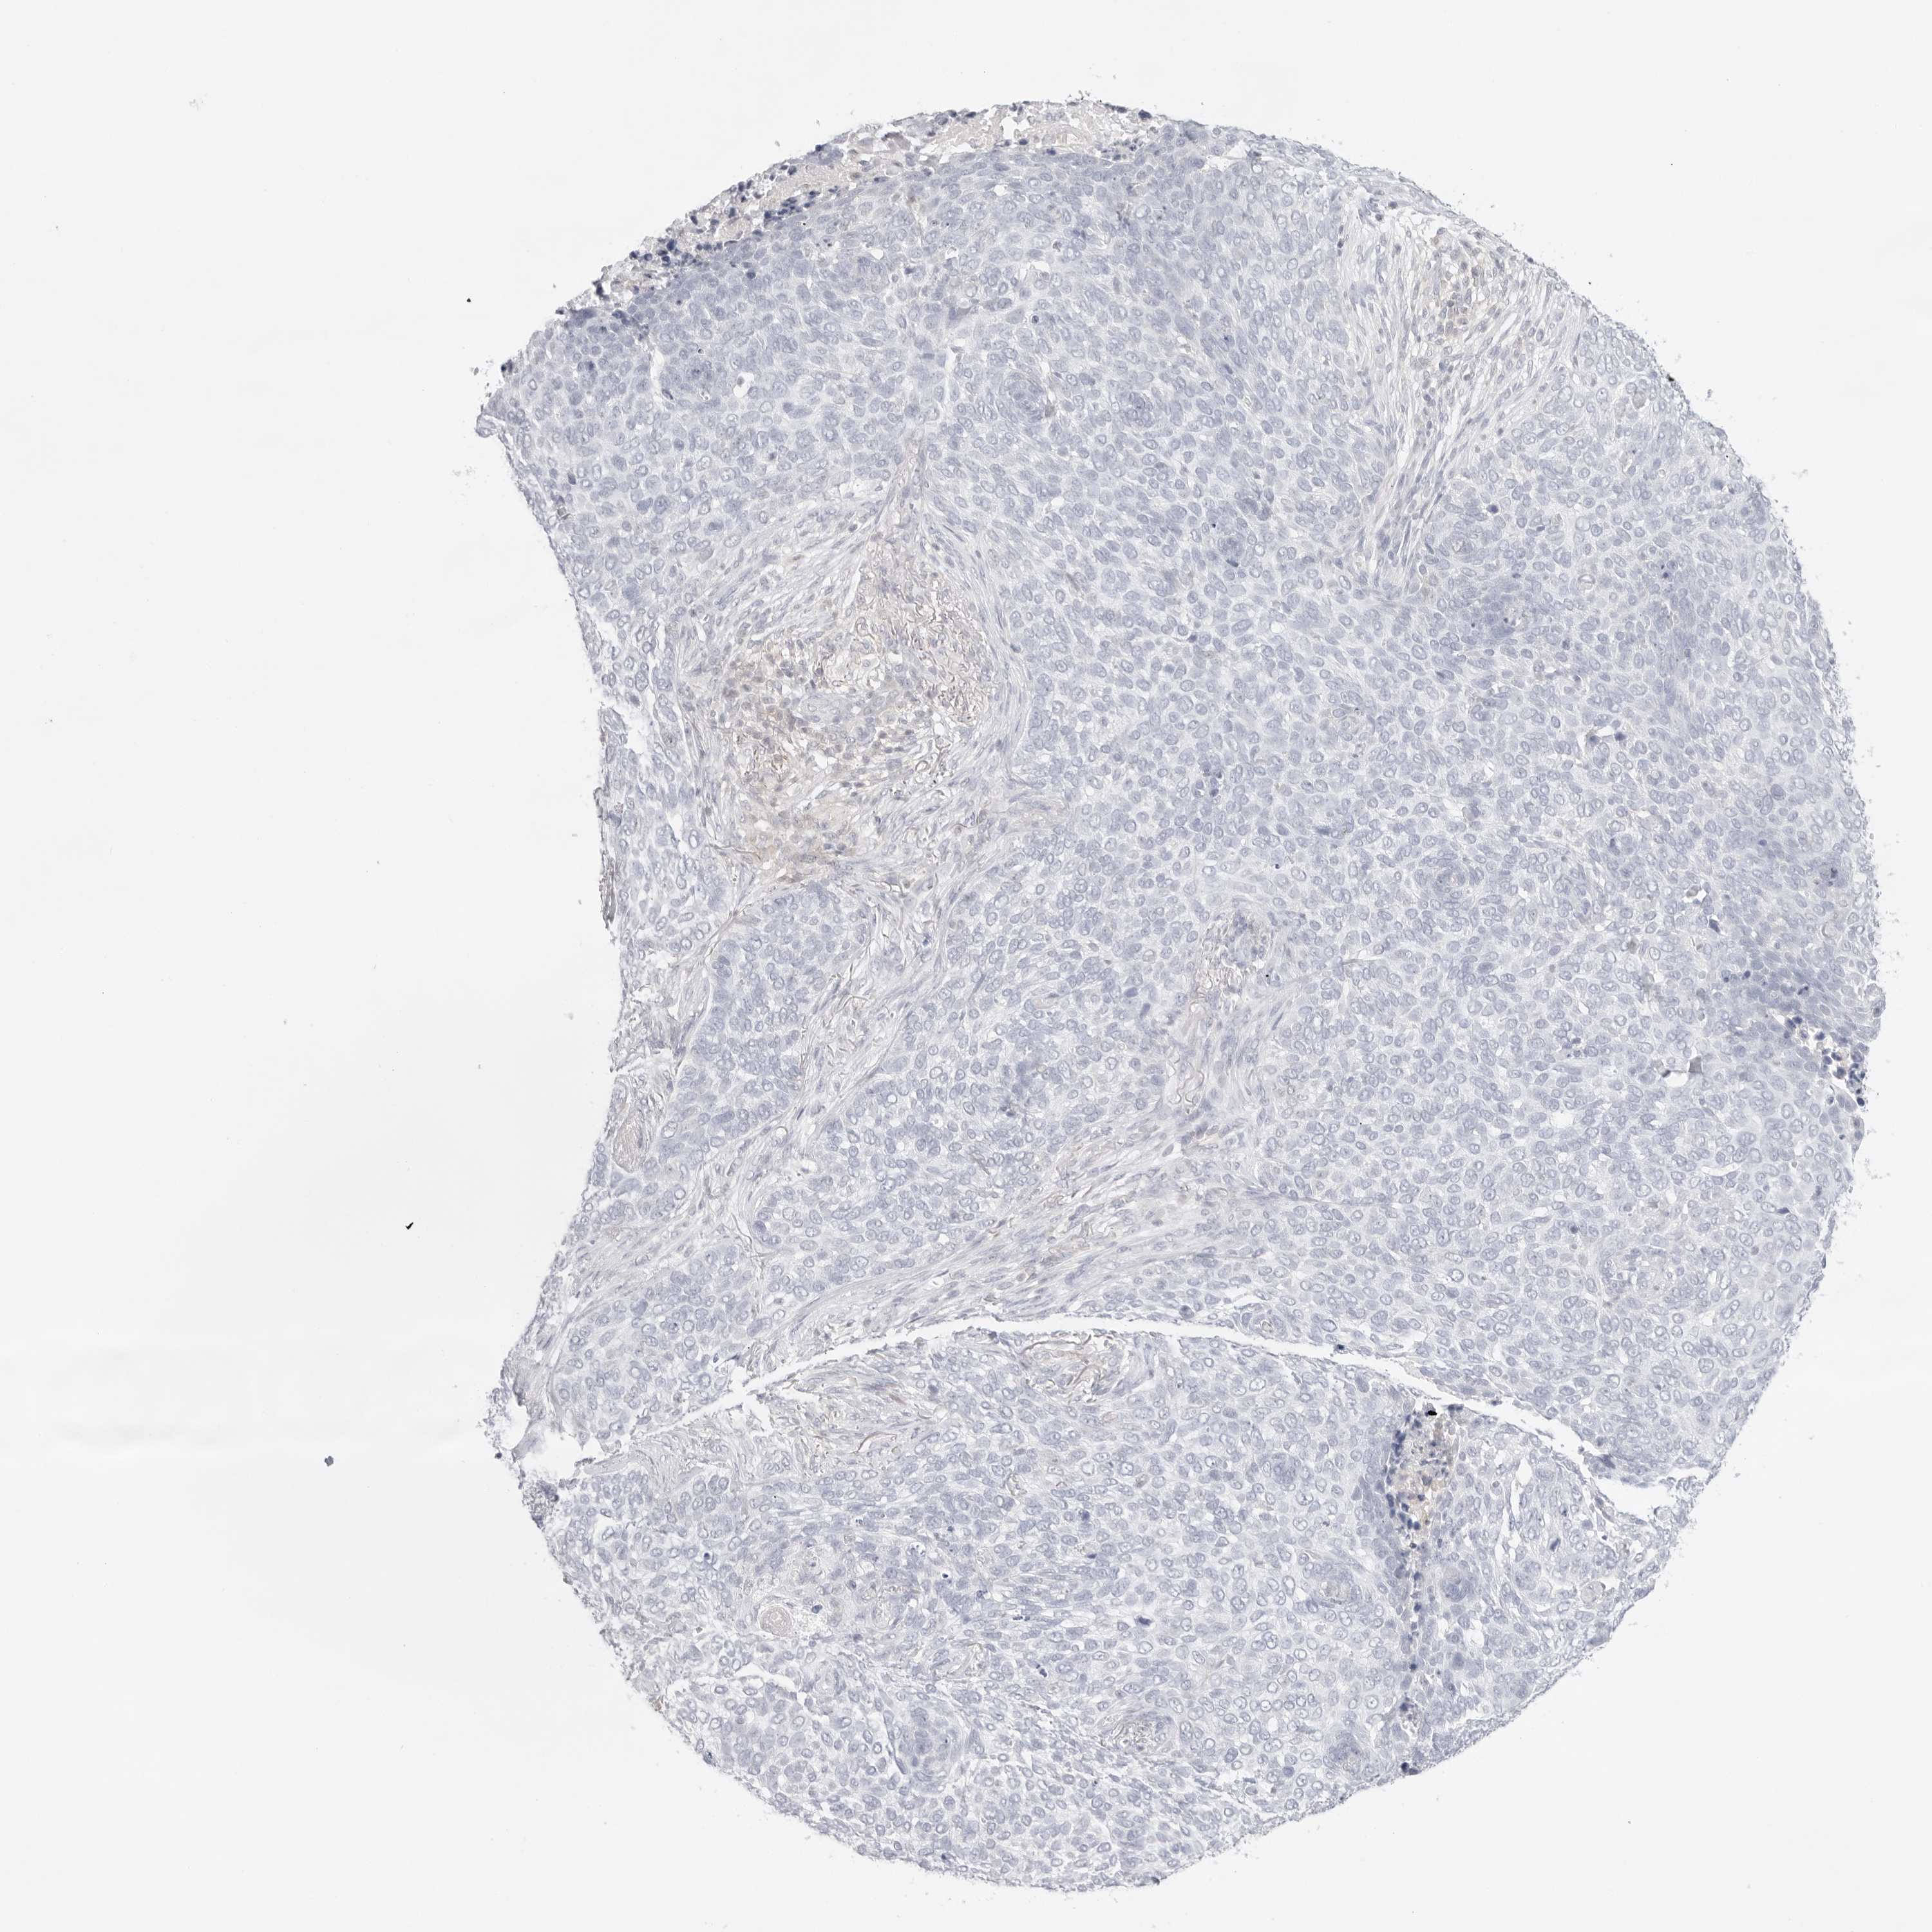

SKIN CANCER - Protein expressioni

A mouse-over function shows sample information and annotation data. Click on an image to view it in a full screen mode. Samples can be filtered based on level of antibody staining by selecting one or several of the following categories: high, medium, low and not detected. The assay and annotation is described here.

Antibody stainingi

Antibody staining in the annotated cell types in the current human tissue is reported as not detected, low, medium, or high, based on conventional immunohistochemistry profiling in selected tissues. This score is based on the combination of the staining intensity and fraction of stained cells.

Each image is clickable and will lead to virtual microscopy that enables deeper exploration of all samples and also displays staining intensity scores, fraction scores and subcellular localization as well as patient and tissue information for each sample.

Antibody HPA006404

Squamous cell carcinoma, NOS